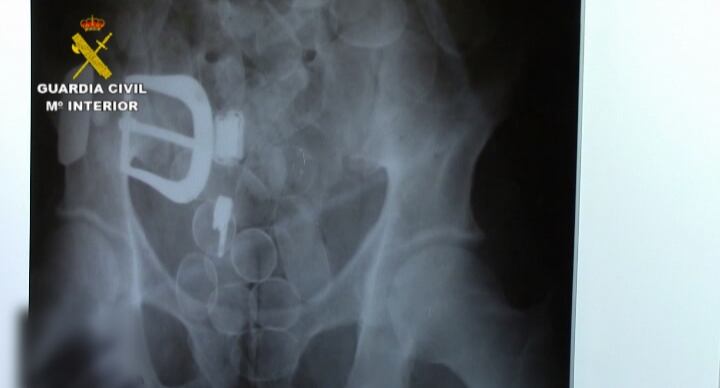

Radiografía de la droga oculta en el cádaver del "mulero" asesinado(CADENA SER)

Un kilo de cocaína en el estómago

Como resultado de la investigación y según se desprendió del resultado de la autopsia, J.A.U.I., falleció por una obstrucción intestinal causada por la gran cantidad de "bellotas" de cocaína que había ingerido, ya que se estima que podría haber alojado en su estómago alrededor de un kilogramo de esta sustancia estupefaciente.

En el cadáver no se hallaron bellotas o restos de droga de una posible rotura de alguna de las bolas de cocaína. Sin embargo, se encontraron restos de analgésicos, que posiblemente le facilitó la organización para mitigar el dolor que tuvo que sufrir hasta que falleció.